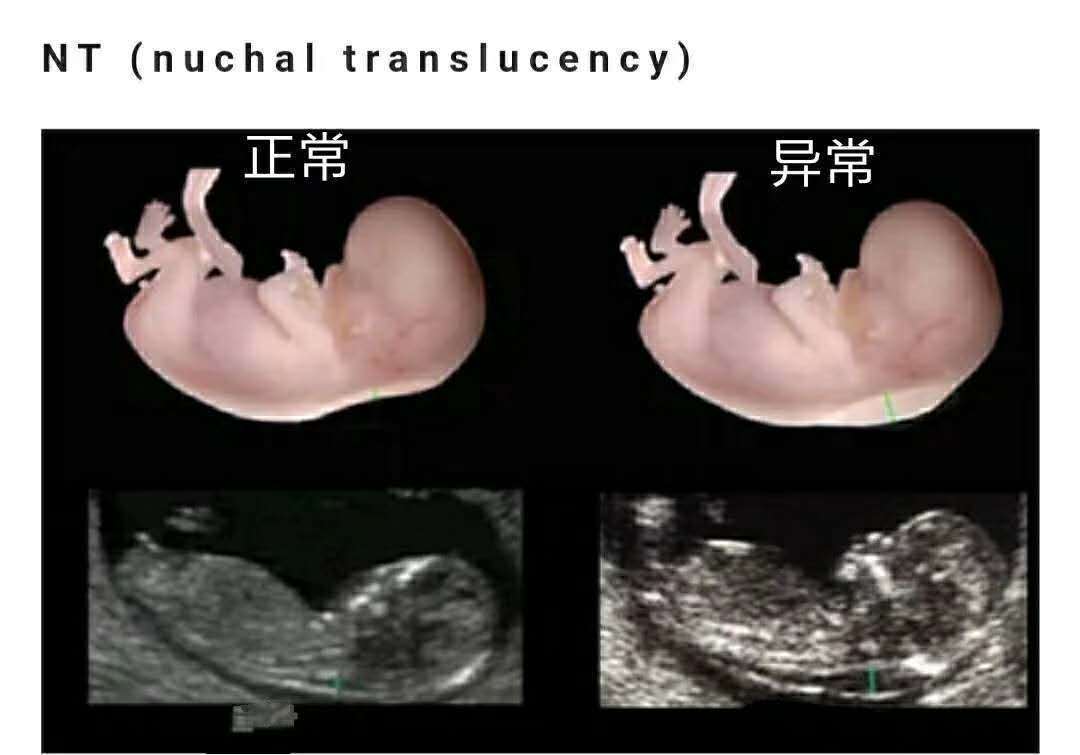

产检这个月最重要的产检就是做NT检查了,它是唐氏筛查的一种手段。因为胎儿尚小,血液流动及淋巴流动不是特别好,所以在怀孕第11至13周+6天这段时间胎儿的颈部会暂时积存淋巴液,而这段时间胎儿的头臀长为45-84mm,是最做NT的黄金时间。为了避免错过检查时间,孕妈要记得提前预约。一般医院会建议你在做完第一次产检(确认怀孕或胎心)时,预约第12周做NT。通常来说,正常的NT值≤3mm,不过即使NT值高于正常范围也不必太担心,NT只是一种筛查手段,只是预示胎儿患唐氏综合症的风险较高。据研究调查表明,NT值为6mm,也有30?概率生出健康宝宝。所以,孕妈要放轻松,提前预约无创DNA或羊水穿刺做进一步的检查。

文章插图